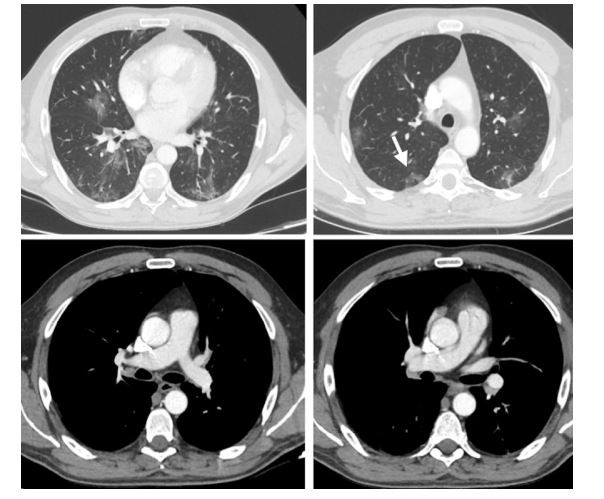

A 48-year-old male patient presented to our institution with symptoms of high fever (38 °C) and abdominal pain for 4 days. He had no respiratory tract symptoms and no abnormal findings on his physical examination and reported no history of respiratory problems. His laboratory workup revealed leukopenia (3.8×10−3 µ/L) and lymphopenia (1.2×10−3 µ/L). Additionally, the following parameters were abnormally elevated: d-dimer (0.7 µg/mL), lactate dehydrogenase (567 U/L), alanine aminotransferase (59 U/L), ferritin (577.8 ng/mL) and CRP (138.2 mg/L). Creatinine and e-GFR were within normal limits. The patient was sent to the radiology department for further evaluation with contrast-enhanced chest and abdominal CT exams. Chest CT demonstrated patchily, ground-glass per lobular opacities with reticular densities at the peripheral portions of both lungs (Fig. 1). Additionally, a reverse halo sign was present in the posterior segment of the right upper lobe. The CT findings were described as possible COVID-19 findings. There were no signs of pulmonary arterial embolism. On the abdominal CT, the right kidney showed patchily, sharply demarcated hypo enhancing and non-enhancing areas in the anterior part of the lower pole with increased heterogeneous linear densities in peri and pararenal areas (Fig. 2). No other abnormalities were seen on the abdominal CT. As a result of clinical and abdominal imaging findings, segmental renal infarct was the patient’s leading diagnosis and he was admitted to our hospital. In the light of chest and renal findings, a polymerase chain reaction (PCR) test from nasal swab for COVID-19 was ordered and urine analysis with urine culture tests was performed. PCR test returned positive for COVID-19 infection. No abnormalities were detected on urinalysis and urine culture was negative. The patient did not develop any respiratory symptoms throughout his hospital course and did not require admission to the intensive care unit. He was treated with hydroxychloroquine and oseltamivir, according to the COVID-19 protocol of our community’s health ministry. In addition, given the renal findings on CT and the diagnosis of renal infarct, the patient was given low-molecular-weight heparin. After the fifth day of the medical treatment, the fever dropped, and his abdominal pain decreased. On the 9th and 11th days of hospitalization, nasal swab for PCR tests were repeated and the results had turned negative on both of those tests. Besides, all of his abdominal symptoms had resolved. Therefore, he was discharged and sent to quarantine at home.

Fig. 1 Peripheral patchy ground-glass peribronchovascular infiltrations are present with reticular densities in both pulmonary lobes. A reverse halo sign is seen in the right lung, upper-posterior segment (arrow). There is no sign of thromboembolism in the major pulmonary arteries